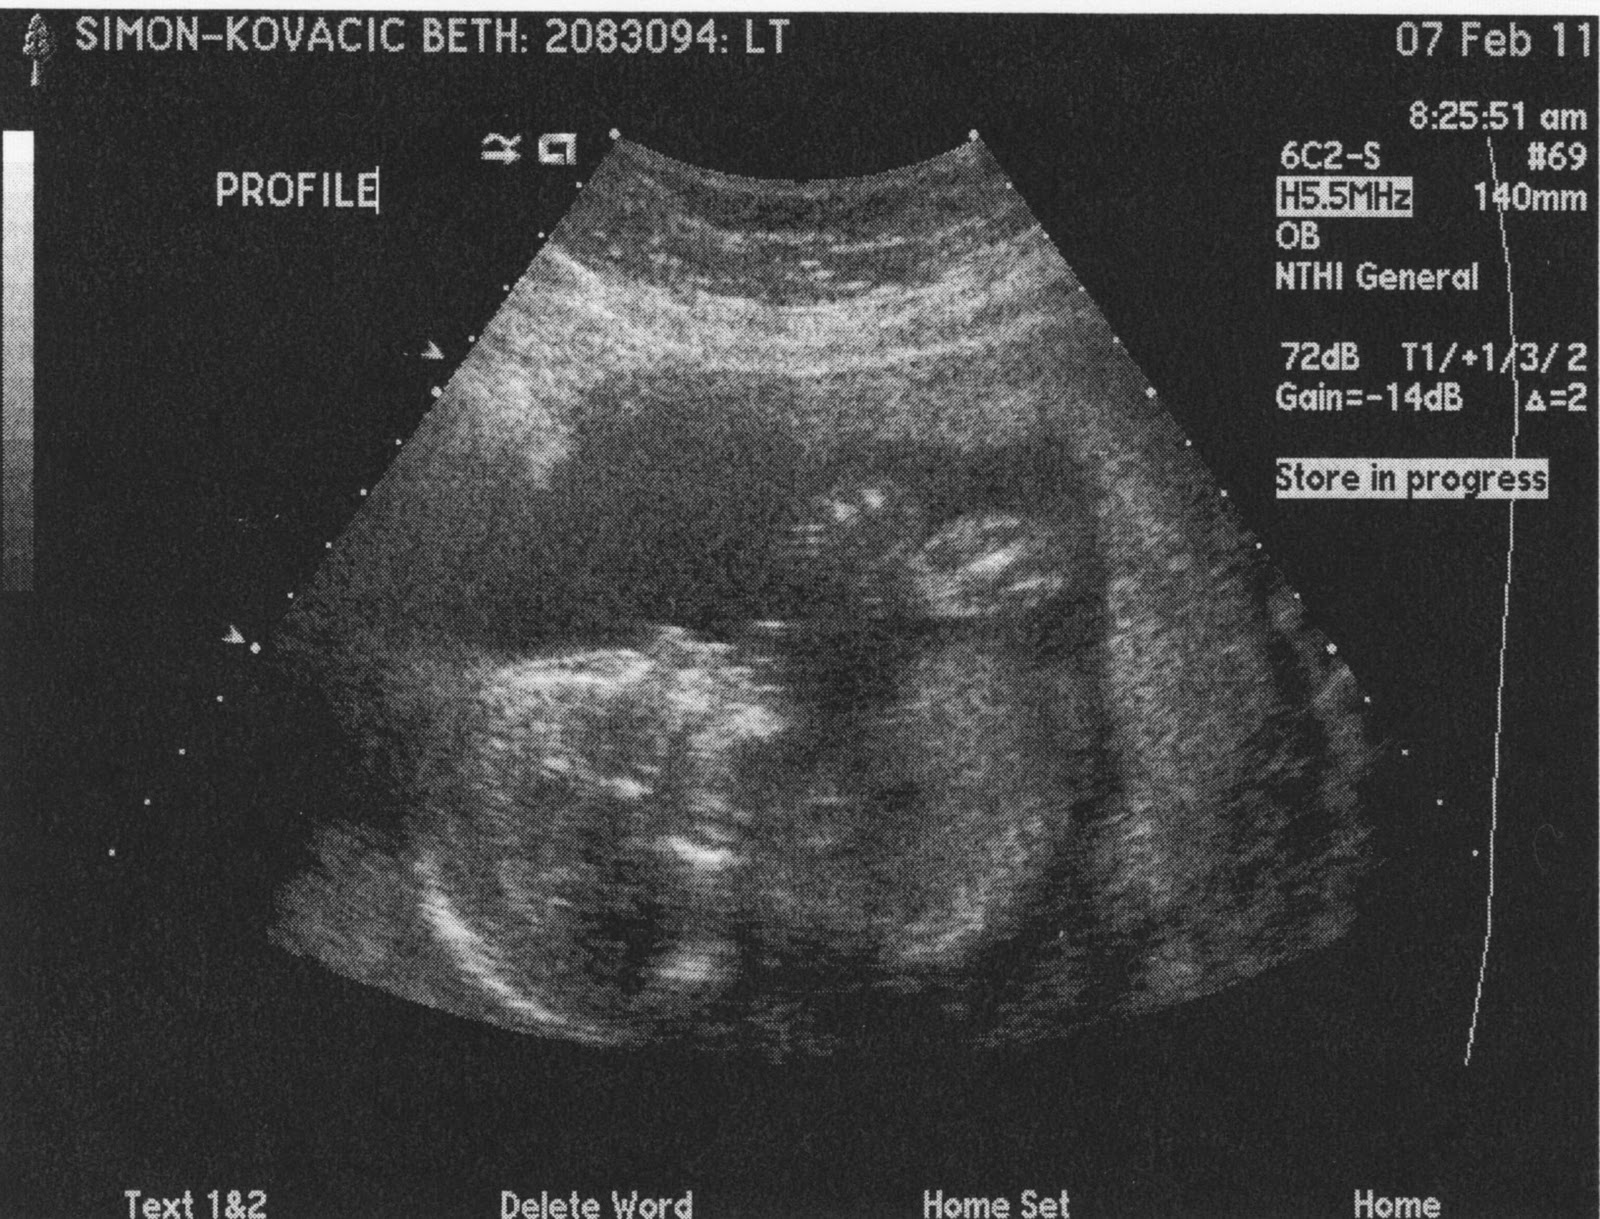

New Baby Pics

I had another ultrasound.  The pictures aren't that great because baby was all folded in half with her feet crossed.  She is measuring right on target, though and everything else looked fine.

First Pictures

Here are the first pictures of our baby girl.